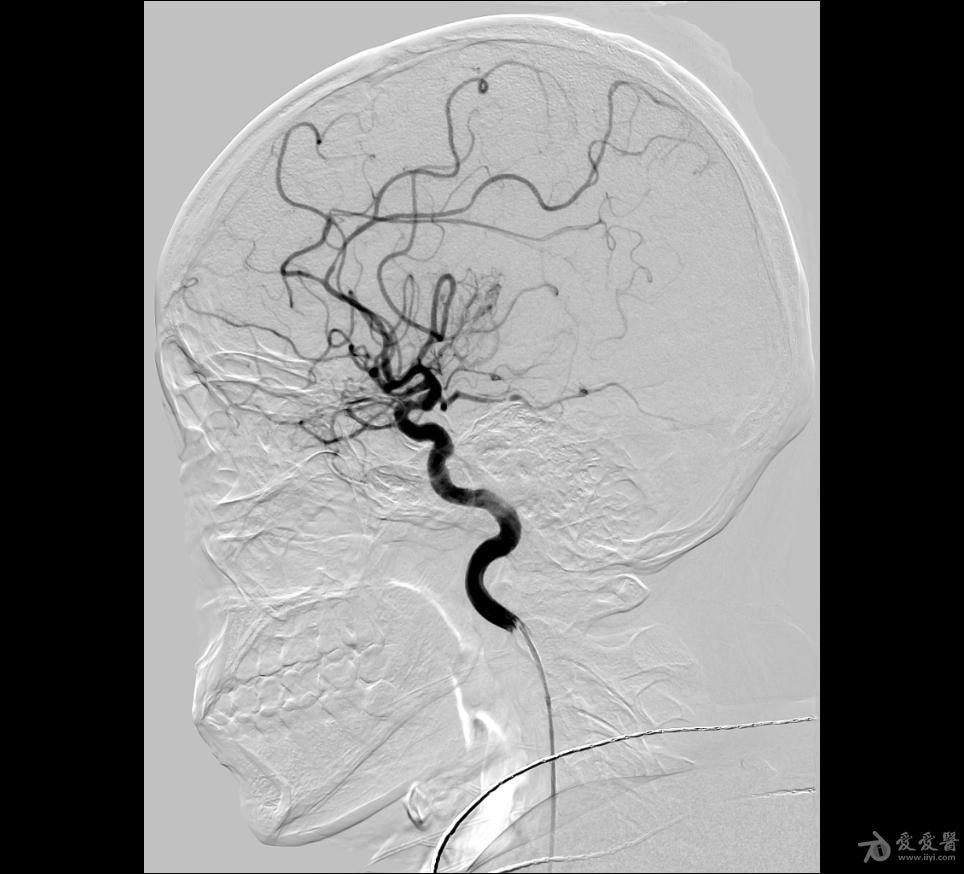

全脑血管造影

全脑血管介入治疗